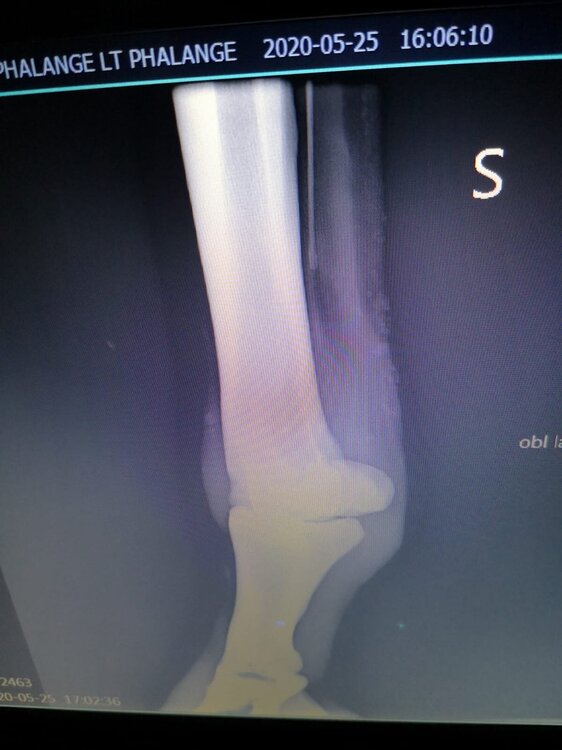

Salve volevo chiedervi qualche informazione in merce tò a un problema che ho avuto con la mia puledra. Qualche settimana fa mentre stavo lavorando alla corda è scivolata urtato l'arto posteriore sinistro. Arrivati in box ho messo dell'acqua a pressione perché si era gonfiato sia il nodello sia il pastorale. Già l'indomani l'arto era sgonfio ritornato normale, quindi ho continuato a lavorarla. Ma dopo qualche giorno di lavoro alla corda leggerissimo, al rientro in box ho notato che sia il nodello che il posturale gonfiavano nuovamente. Allora ho chiamato il veterinario che ha detto che la cavalla aveva una lussazione e mi ha insegnato come cura una fasciatura con della creta per 24h per cinque giorni e un antinfiammatorio. Dopo un paio di giorni la fasciatura ha fatto come delle vesciche e il gonfiore è aumentato dal pastorale alla garra. Abbiamo chiamato un altro veterinario abbiamo fatto vedere anche a lui la cavalla e diceva che poteva essere la frattura del ditino, ma si dovevano fare le lastre per essere sicuri. Ora abbiamo fatto le lastre e il radiologo dice che c'è dell'infiammazione ma non c'è niente di grave. Il veterinario,viste le lastre dice che deve essere operata. Allora abbiamo consultato un'altro veterinario che dice che la cavalla non ha assolutamente niente. Ora io vi allego le radiografie, datemi un vostro parere perché non só più cosa fare. Grazie